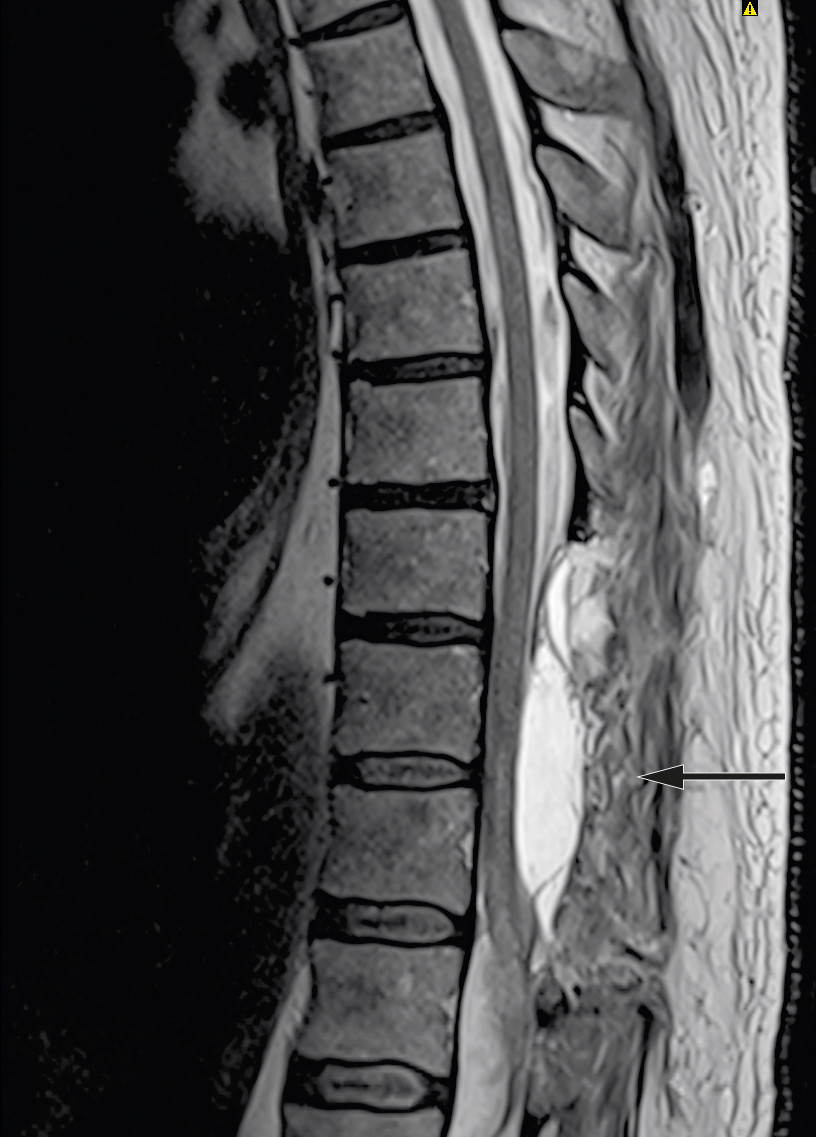

Pasienten hadde ingen bedring i nevrologisk status postoperativt. Det ble startet behandling med dalteparin (Fragmin, 5 000 IE subkutant × 1) første postoperative dag, og han ble rutinemessig behandlet på intensivavdeling med middelblodtrykk (mean arterial pressure, MAP) over 85 mm Hg den første uken (7). MR-undersøkelse ble gjentatt etter ti dager og viste tilkommet epidural cerebrospinalvæskeansamling i nivå Th10–11 med kompresjon av ryggmargen (figur 3). På grunn av hodepine og kvalme supplerte man med MR av hodet. Denne viste litt intraventrikulært og subaraknoidalt blod, som ble tolket som distribuert fra den spinale blødningen.